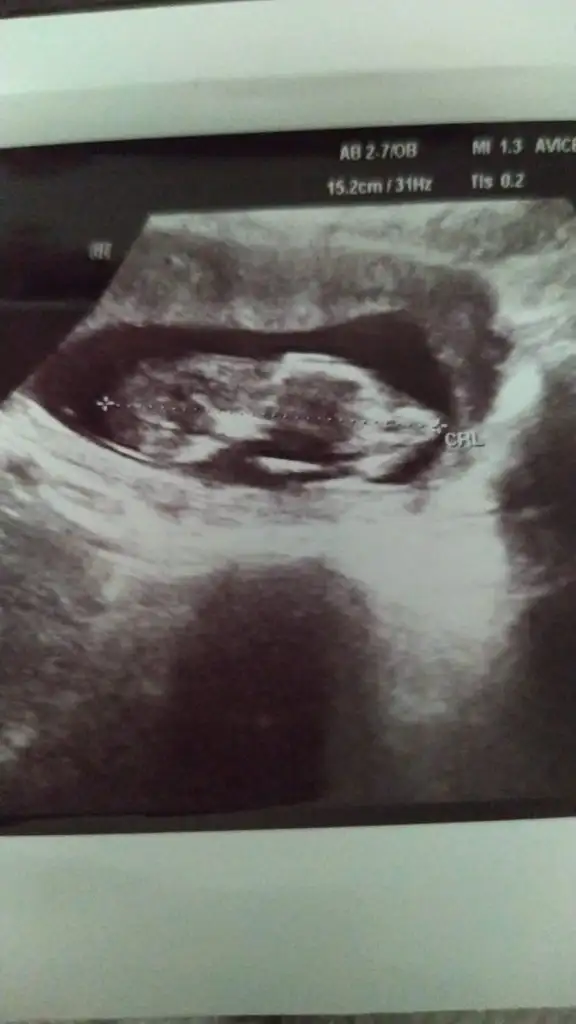

Selamlar herkese 😊 sabah doktora gittim baya büyümüş 🙈👶🏼 bes alti tup kan alindi hem kan testi hem ikili test icin bir de idrar tahlili istedi doktor. İnşallah güzel çıkacak sonuçlar 🙏

T tulperde rica etsem tahmin alabilir miyim cok arada kaldım 🙈 doktor bisey demedi